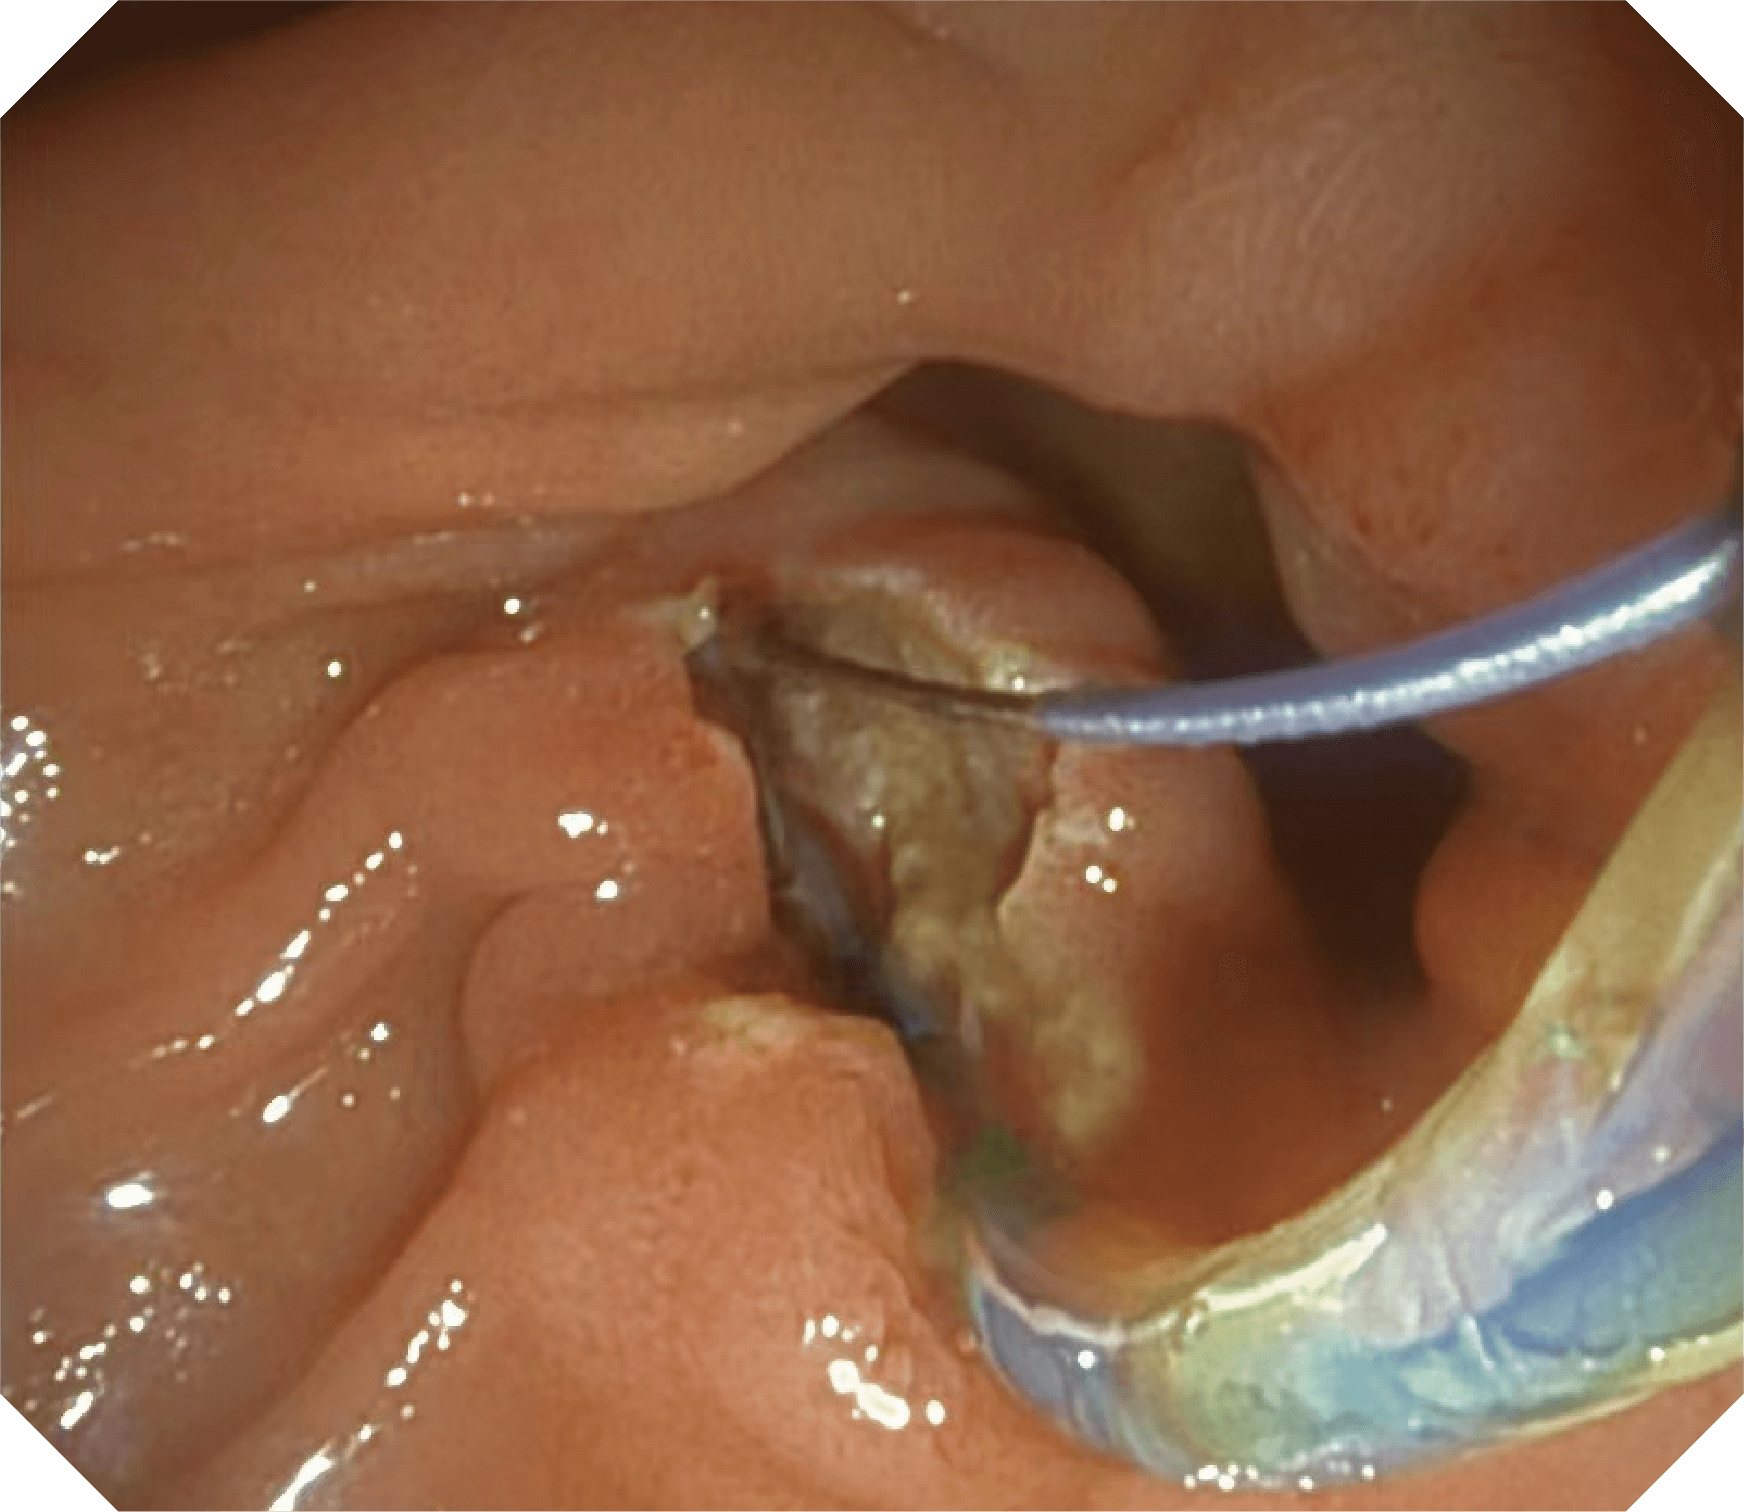

4.2mm大钳道,器械交换更顺畅

优异的手术器械抬举性

当切开刀伸出视野外时,导向面引导其回归视野